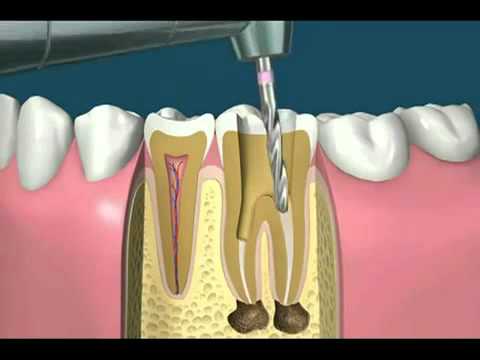

Root Canal |

Root canal treatment is used to repair and save a tooth that is badly decayed or becomes infected. During a root canal procedure, the nerve and pulp are removed and the inside of the tooth is cleaned thoroughly and then sealed. Without this treatment, the tissue surrounding the tooth will become infected and abscesses may form eventually leading to tooth extraction. Often a full coverage restoration like an onlay or crown is needed post root canal.